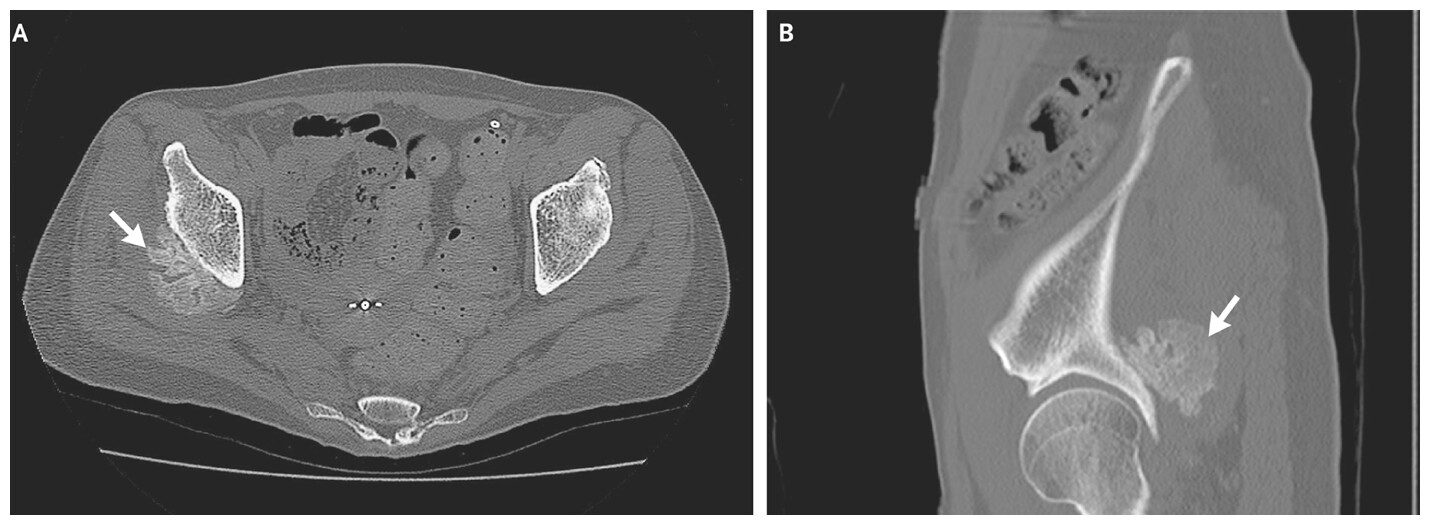

Initial plain radiographs of the pelvis were unremarkable. This is consistent with the natural history of myositis ossificans, as early radiographic findings are often absent or nonspecific during the initial inflammatory phase. Because the patient’s pain persisted, computed tomography (CT) was performed one month later. CT imaging revealed a well-defined calcified mass within the gluteus minimus muscle, with evidence of trabecular bone formation and a surrounding cortical rim. These features are characteristic of mature myositis ossificans and help distinguish it from malignant soft tissue tumors or infectious processes.

Myositis ossificans typically progresses through three stages: an early inflammatory phase, an intermediate osteogenic phase, and a mature phase characterized by organized lamellar bone formation. During the early stage, patients often experience pain, swelling, and restricted joint movement, while imaging studies may be normal or show only soft tissue edema. As the condition evolves, peripheral mineralization becomes apparent, often described as the “zonal phenomenon,” in which mature bone forms at the periphery and less organized tissue occupies the center. This pattern is best visualized on CT and is a key diagnostic feature.